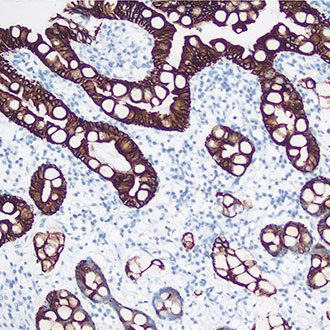

CAM5.2

CAM5.2 -